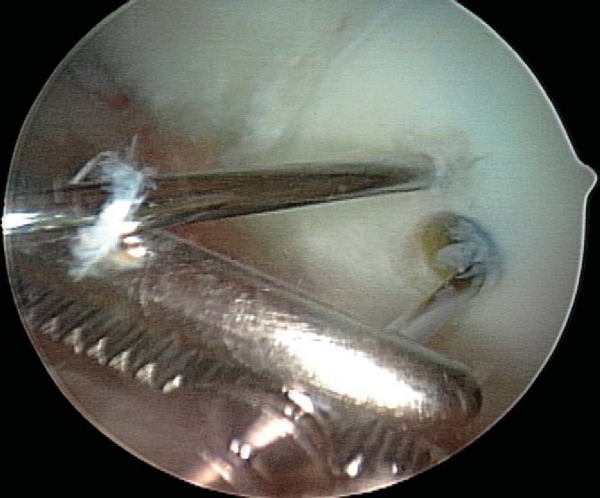

Use of nonabsorbable fixation typically requires a second procedure for implant removal. Implant removal can almost always be accomplished arthroscopically, regardless of whether initial fixation was obtained by open or arthroscopic technique. A diagnostic arthroscopy is performed to re-evaluate the joint and to assess healing of the lesion by arthroscopic visualization and palpation. Spinal needle localization is used to establish the appropriate vector for implant removal (

Fig. 53-13

). A noncannulated screwdriver is used to initiate screw removal because a sufficient amount of torque may be applied during this process to fracture the tip of a cannulated screwdriver. Once the screw has been backed out over several turns, a guide wire is threaded down the shaft of the screw and a cannulated screwdriver completes removal. Once the tip of the screw has been disengaged from the articular surface, the guide wire is clamped with a hemostat at a point distal to the tip of the screw to prevent loss of the screw in the joint or extra-articular soft tissue (

Fig. 53-14

). The lesion should then be probed for stability and the knee brought through a cycle of flexion-extension (

Fig. 53-15

).